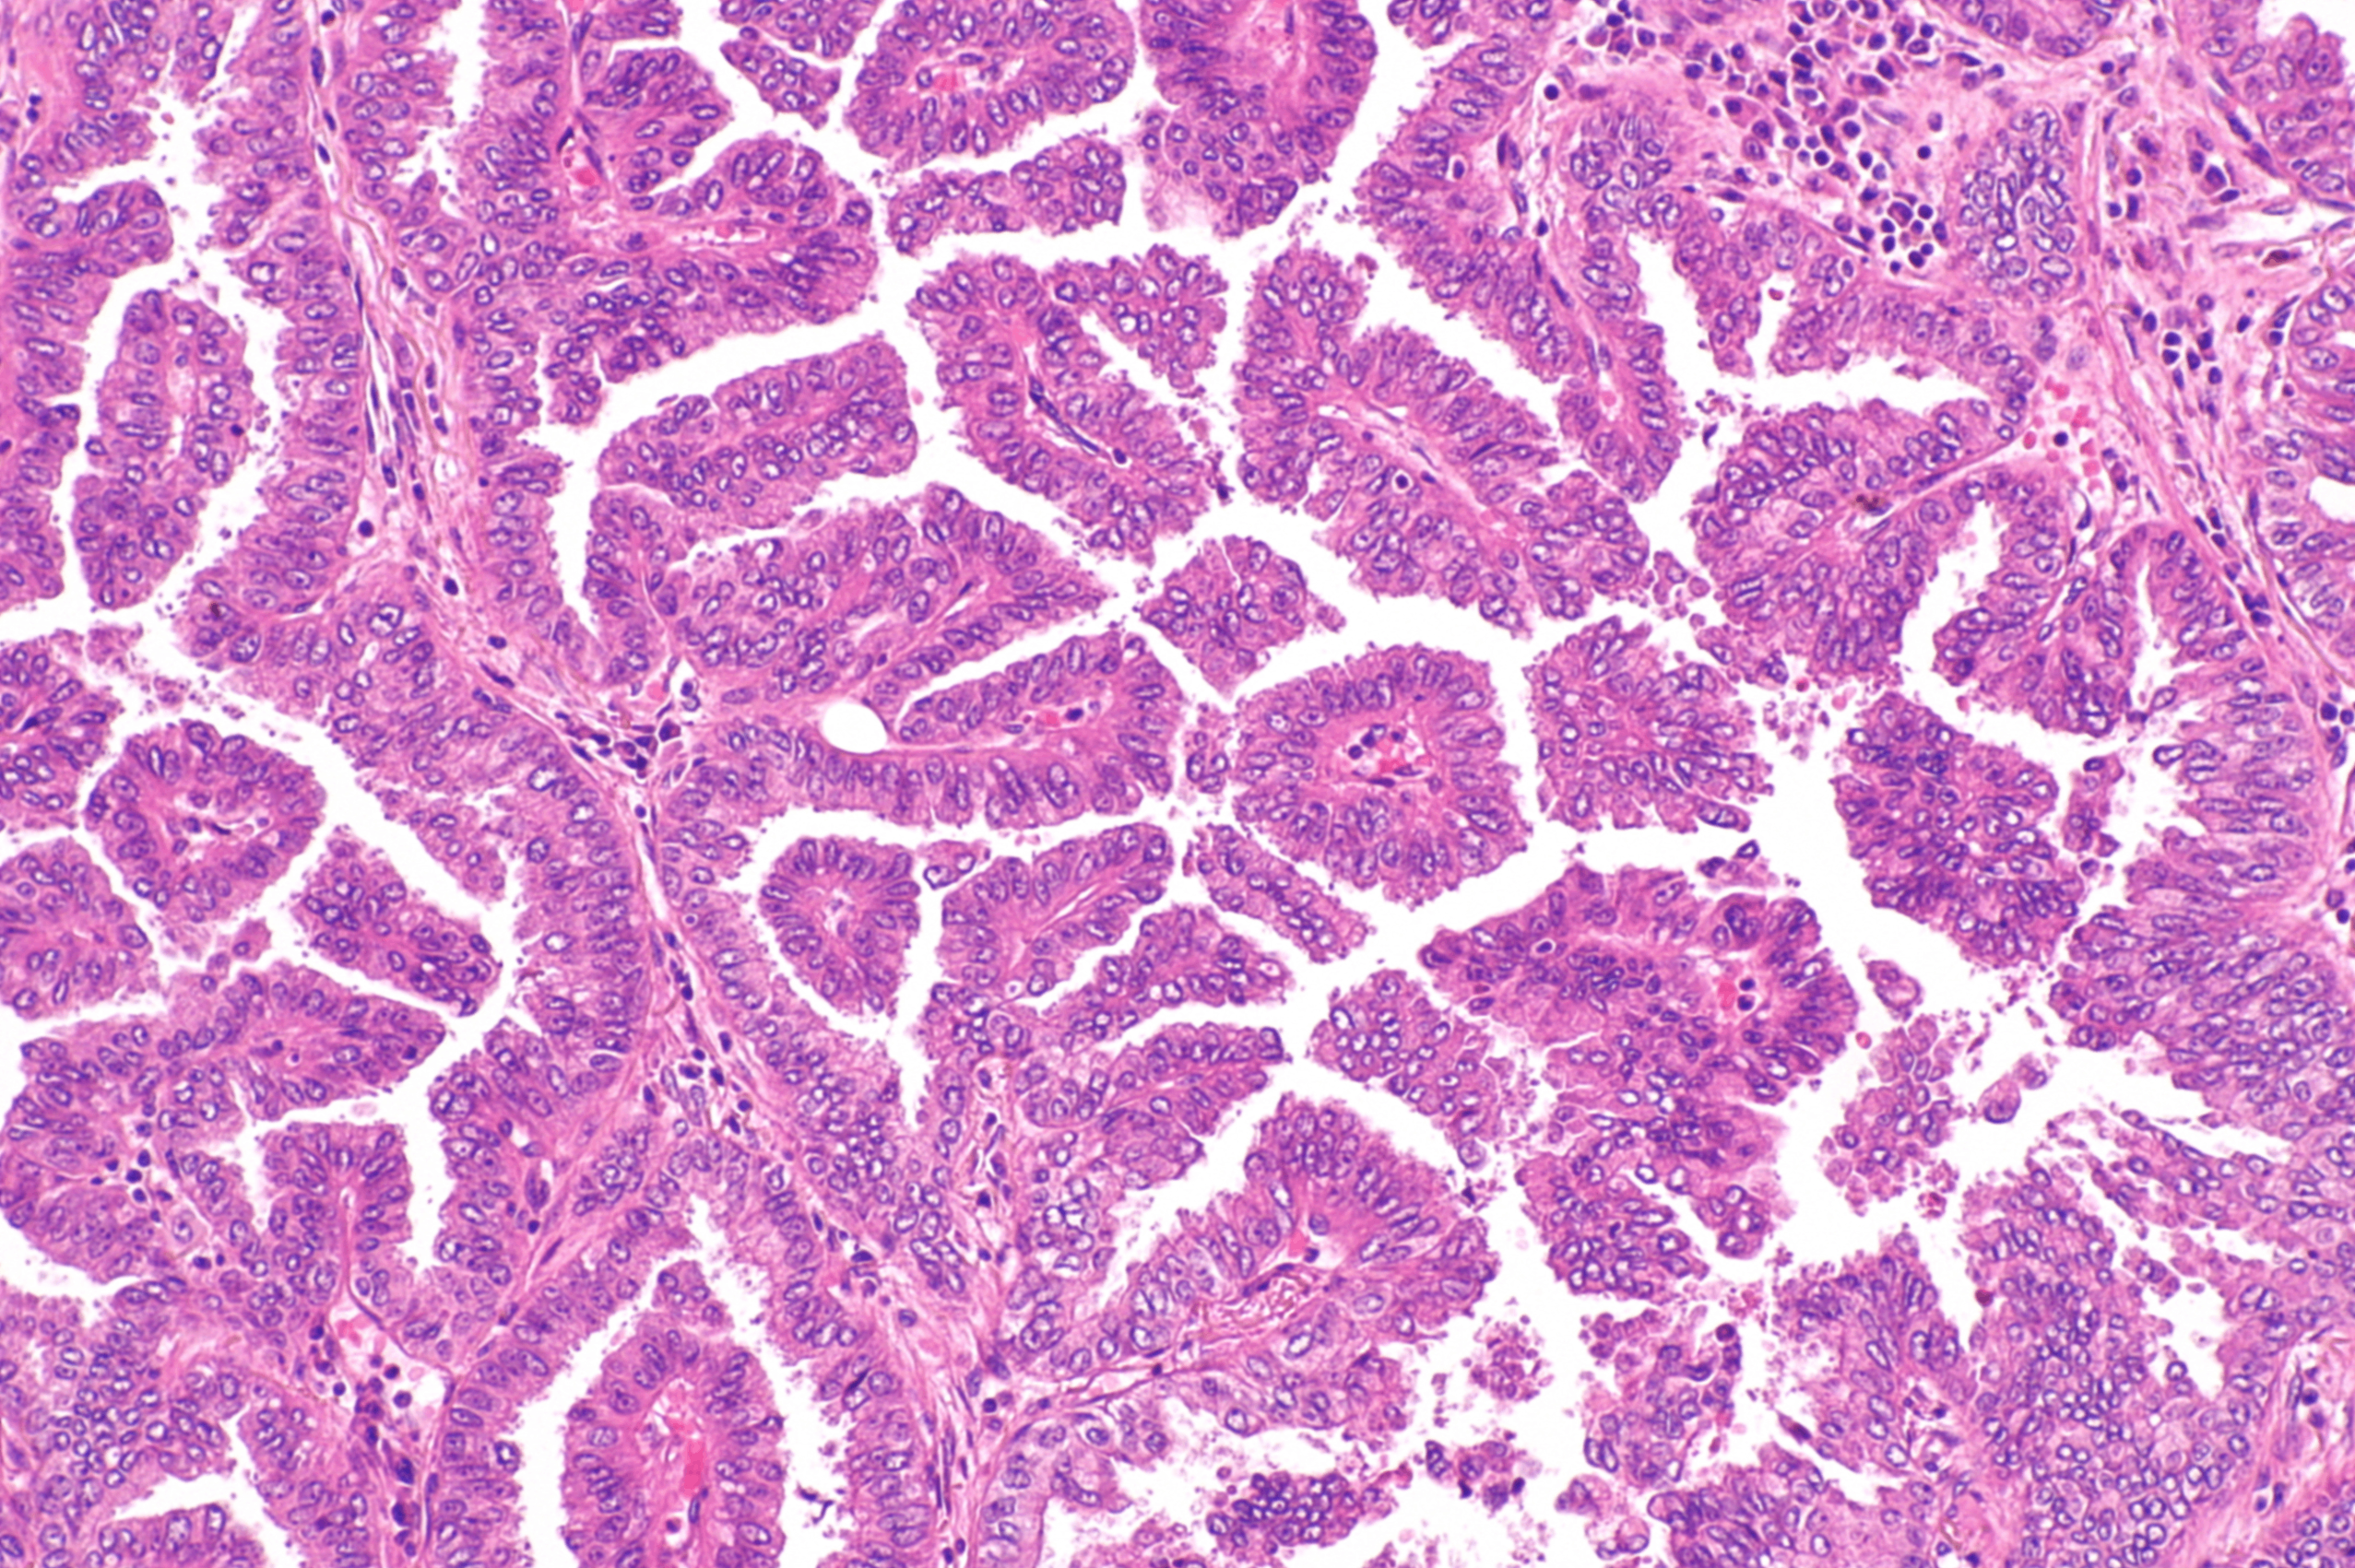

• 조직학적 특징

- 비정상적인 샘조직이 lepidic, papillary, micropapillary, 또는 solid 형태로 증식

- mucin-producing subtype 또한 존재

Papillary adenocarcinoma of the lung, Wikimedia Commons

Mucinous adenocarcinoma of the lung, Wikimedia Commons